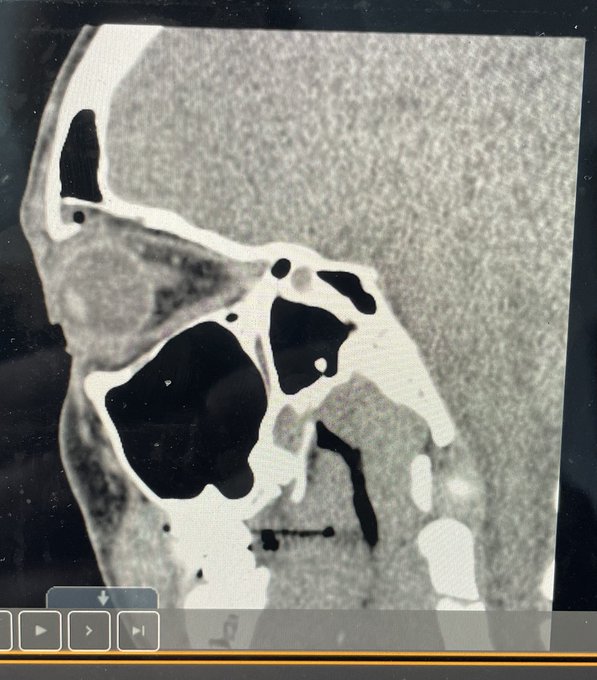

WWE spricht von einer Augenhöhlenfraktur

„Nach dem brutalen Angriff wurde bekannt, dass ‚The Nightmare‘ einen Bruch der rechten Augenhöhle erlitten hat, was Ripley für eine unbestimmte Zeit außer Gefecht setzen wird.“

Auf Social Media zeigt WWE dazu ein Röntgenbild der vermeintlichen Verletzung.

Anfangs war unklar, ob Ripley tatsächlich die von WWE genannte Verletzung erlitten hat oder eine andere medizinische Situation vorliegt. Mittlerweile ist die Verletzung gegenüber Power-Wrestling allerdings bestätigt worden. Eine solche Fraktur des rechten Augenhöhlenknochens dürfte eine mehrmonatige Pause zur Folge haben.